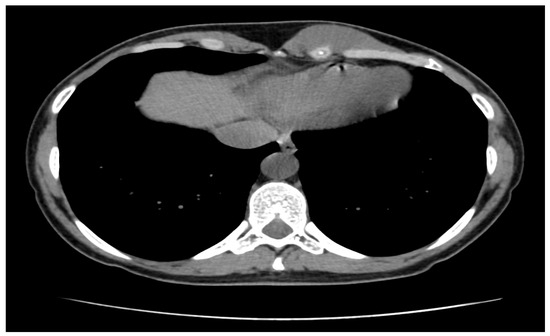

3.1. Diagnosis and Imaging Characteristics